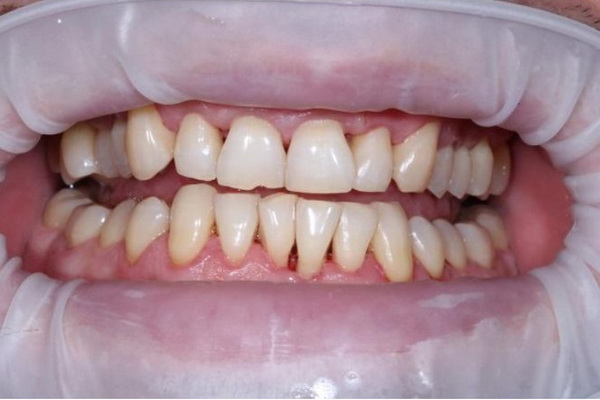

Стан ясен та зубів через 8 місяців після лікування (до та після проведення планової професійної гігієни ротової порожнини).